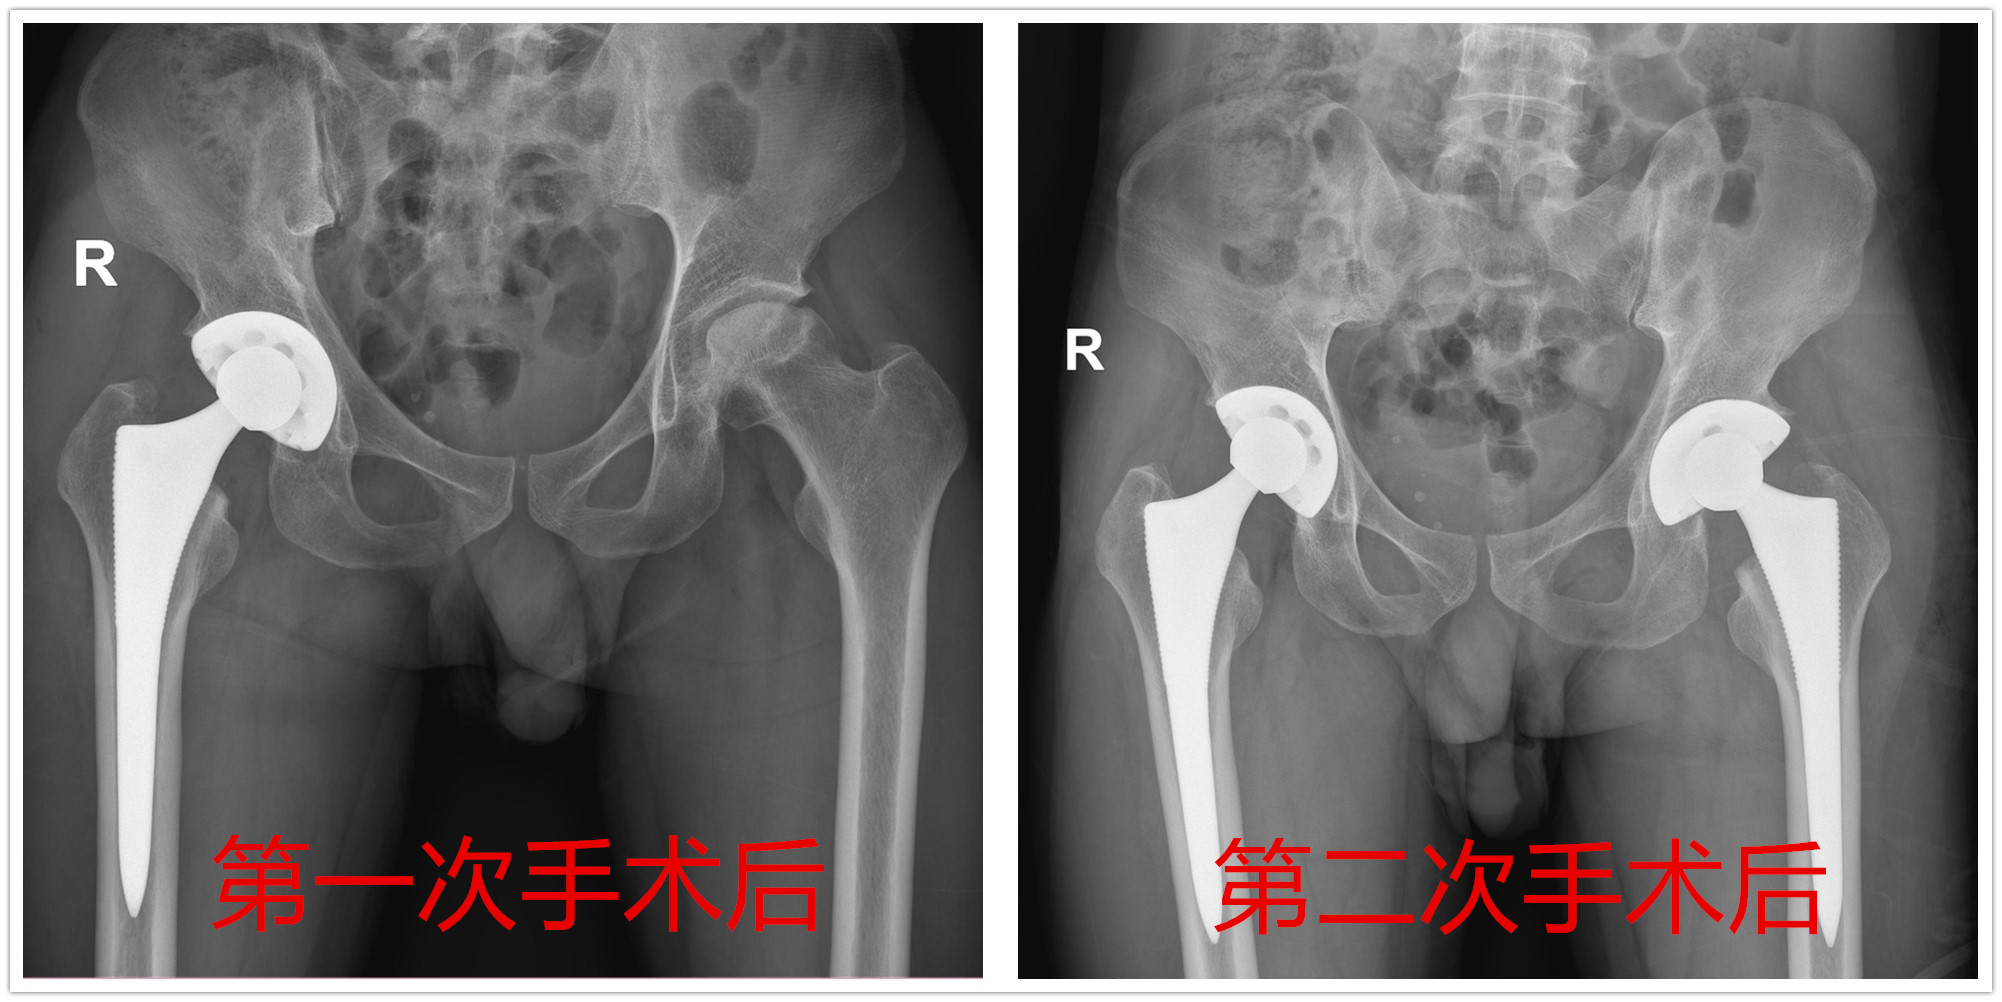

术前:双侧股骨头坏死

术前:双侧股骨头坏死

小李病情确诊后先进行了保守治疗,但治疗效果较差,4年来,髋部疼痛一直折磨着他。后经与家人商量,决定还是选择手术治疗。2020年11月,小李入住我院骨一科,先将疼痛较重的右侧进行了“全髋关节置换术”,术后第2天就下地行走了,慢慢右下肢恢复了正常。见右侧完全恢复好后,今年7月,骨一科为他进行了左侧全髋关节置换术,经过1个月休养,目前小李恢复良好,已经可以正常工作和生活。